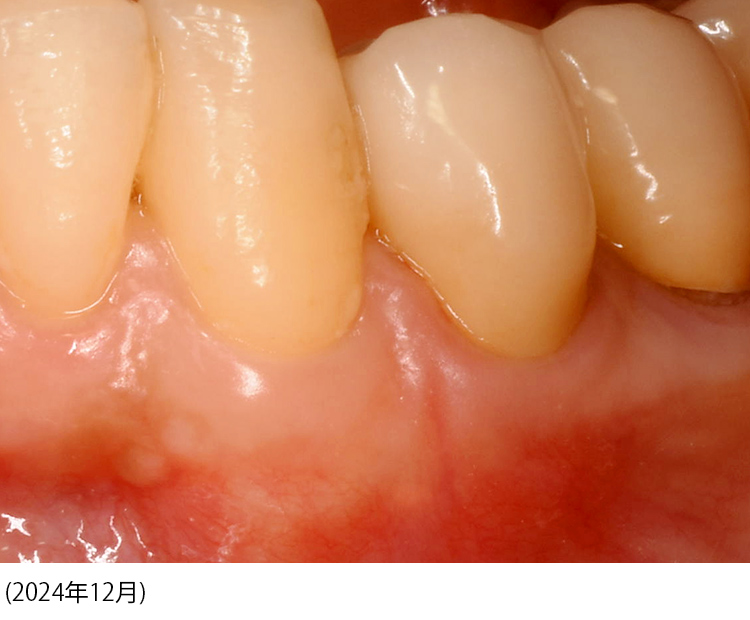

※自宅保管のため神経質な方はご遠慮ください※著者による前所有者向けのサイン記入されています。必要なければカットします。審美修復治療 : 複雑な補綴のマネージメント」山崎 長郎定価: 36000円+税箱の裏側に1箇所汚れがございますが、本自体には汚れはないので目立った汚れなしにしております。